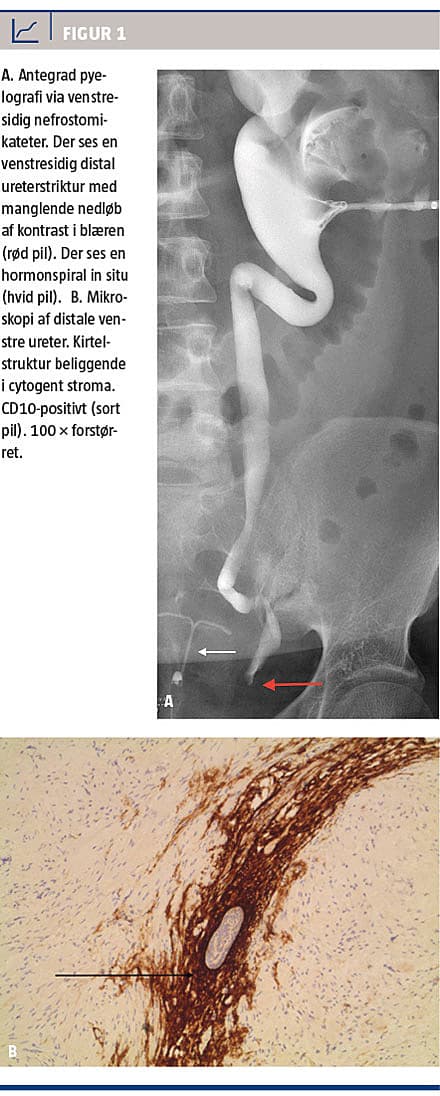

Da infektionen var under kontrol, blev der foretaget antegrad pyelografi, hvor man fandt en 2 cm distal venstresidig ureterstriktur lige før ureters indløb i blæren (Figur 1A). CT af abdomen viste atrofisk venstre nyre. Der blev foretaget forsøg på diagnostisk ureteroskopi med biopsi, men denne kunne ikke gennemføres pga. den udtalte ureterstriktur.

Fire uger efter indlæggelsen blev det ved renografi påvist, at venstre nyres funktionsandel udgjorde 23% af den samlede nyrefunktion. Trods relevant systemisk antibiotika var patientens almene tilstand i den følgende måned svingende med fluktuerende temperaturer, infektionstal og kreatininniveauer, intermitterende makroskopisk hæmaturi og anæmi samt svingende

produktion i nefrostomien. Årsagen til ureterstrikturen

forblev ukendt trods såvel gynækologisk som organkirurgisk udredning. Efter otte ugers insufficient behandlingsrespons på infektionen og svær distal ureterstriktur blev der foretaget venstresidig nefroureterektomi. Operationen forløb ukompliceret, og patienten blev udskrevet efter få dage. Patologisvaret viste, at venstre nyre havde kronisk inflammation og akut abscederende inflammation. I den distale del af ureter fandtes inflammatoriske forandringer, fibrose og små øer af endometroidt væv, hvilket er diagnostisk for ureteral endometriose.